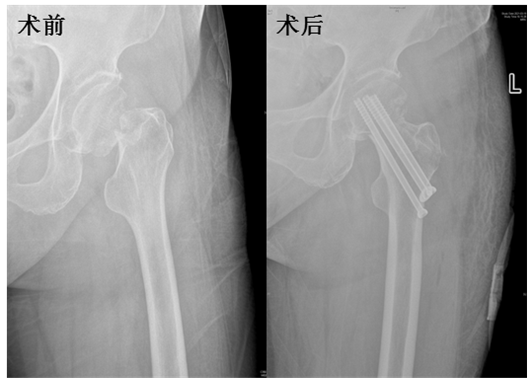

与此同时,受张英泽院士委派前来我院指导临床工作的连晓东教授带领创伤外科团队为一例股骨颈骨折患者进行手术。针对股骨颈骨折空心钉内固定术后骨折不愈合、股骨头坏死发生率高的问题,张英泽院士团队发明了股骨头钻孔减压、游离髂骨块30°角植骨、空心钉内固定术,能够有效预防内固定术后骨折不愈合,并在一定程度上降低股骨头坏死率。该例股骨颈骨折患者为头下型骨折,手术难度较大,连晓东教授采用全新术式,手术顺利完成。